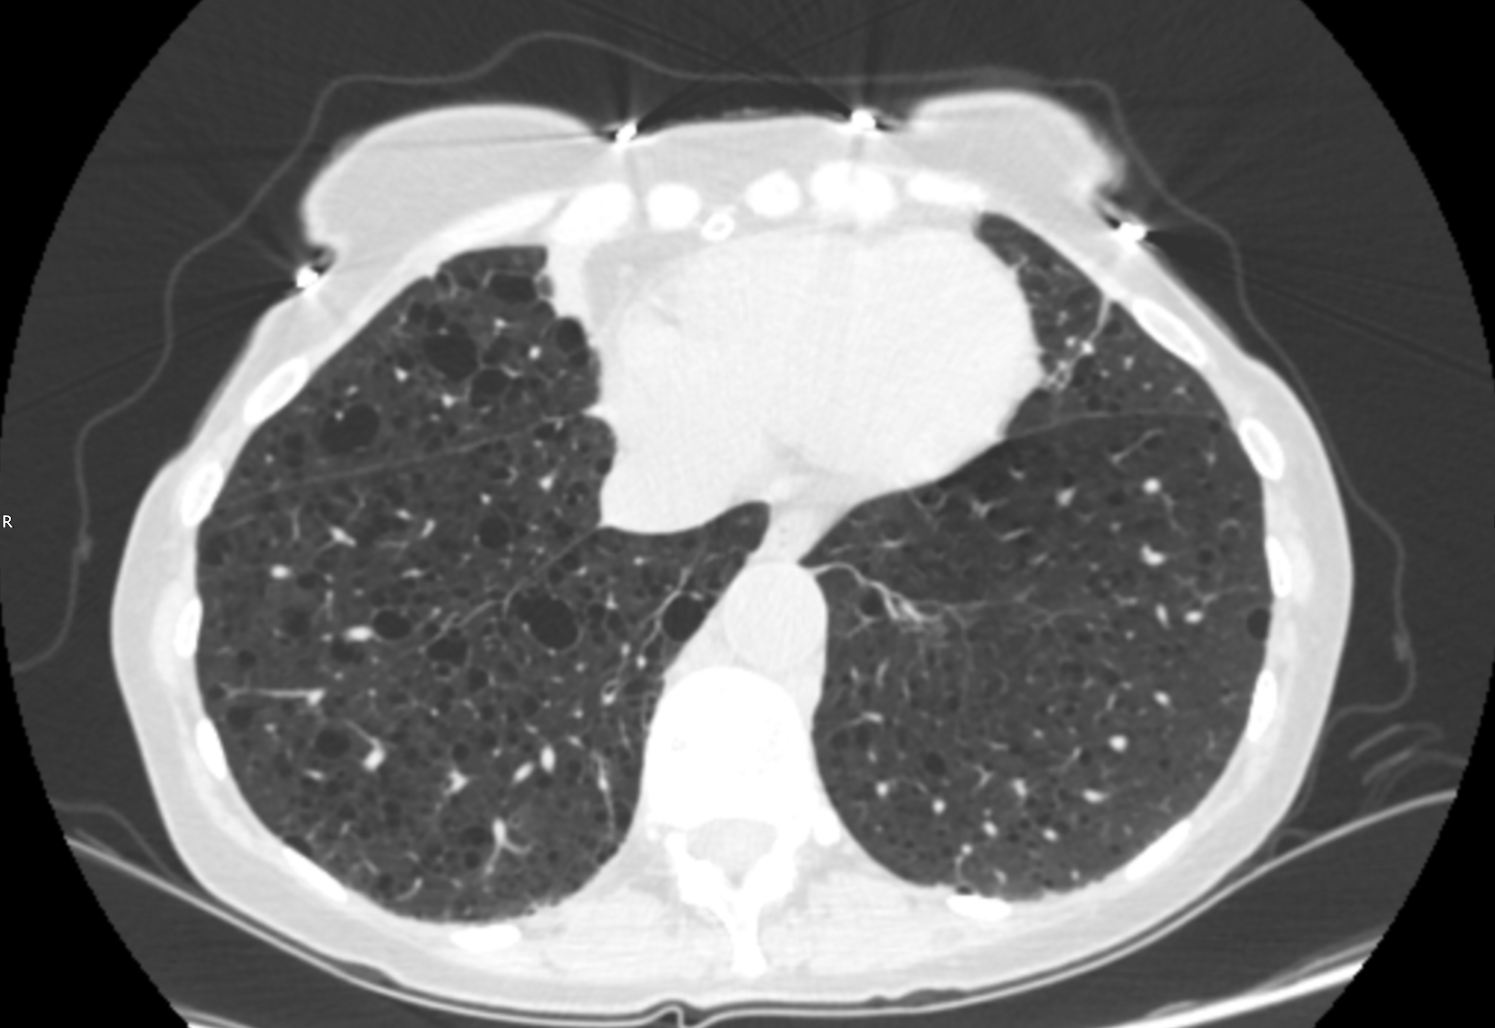

A 45 year old female patient was referred by her GP for a renal ultrasound to investigate hypertension resistant to drug treatment. She was otherwise in good health and had no previous medical history of note or relevant family history. Representative ultrasound images of the kidneys are shown in Figures 1 and 2.